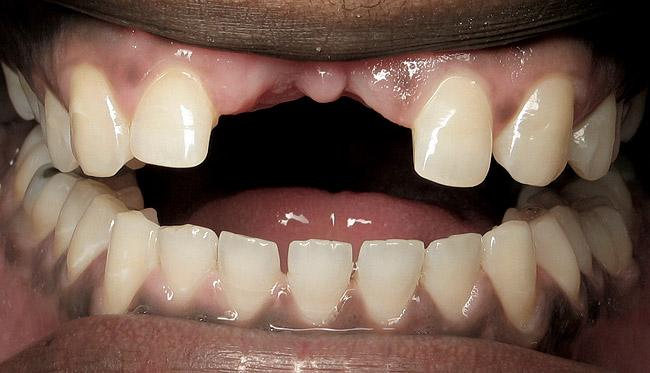

The decision to retain or extract a questionable tooth is one that occurs frequently in dental practice. There are many factors to consider when making this decision. Some situations are very straightforward (Figure 1) while others fall into a “gray” area of decision-making (Figure 2). This article will provide guidelines for determining whether to extract or retain a tooth when the decision is not so straightforward using structural, periodontal, endodontic, and esthetic criteria. Some teeth may involve only one of these areas, and some will involve various combinations of these areas. There are also other important factors to consider such as patient expectations, patient finances, and patient compliance, but these topics vary from patient to patient and should be discussed with each individual patient. While these topics are very important to the decision-making process, they are beyond the scope of this article.